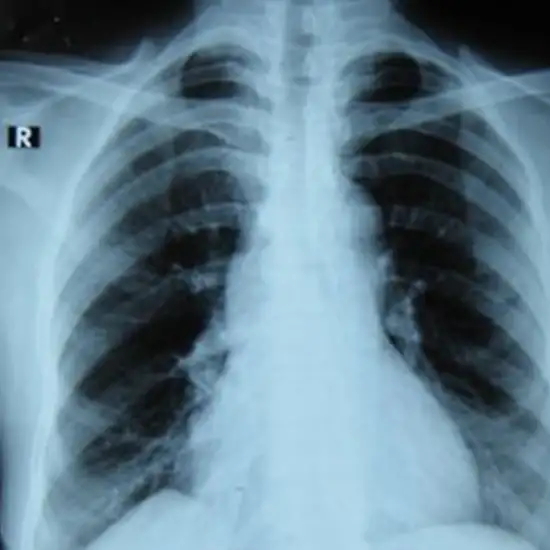

x-ray pft pulmonary function test

X-Ray PFT

What is an X-ray Pulmonary Function Test (PFT)?

Pulmonary function tests (PFTs) are a series of tests that evaluate the health of your lungs. Lung volume, flow, and gas exchange are measured. This includes your ability to breathe and your lungs' ability to transport oxygen throughout your body.